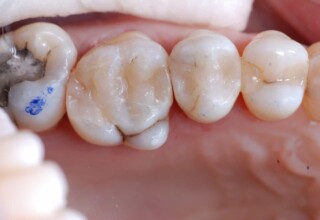

Posterior Tooth Root Canal Restoration with a Composite Resin Filling

The common restoration of a posterior tooth after a root canal is a crown. Its main purpose is to protect from fracture and concomitant extraction. In very few cases that specific criteria (mainly remaining tooth structure) are met or where finances predominate, an extensive composite filling can restore both aesthetics and function.

Restoration of a cracked molar with composite resin

Cracked teeth present a challenge in restorative dentistry both from the aspect of complexity of the restoration itself (usually large filings) and the necessary providings to avoid a complete fracture. The presented case demonstrates the simplest approach of a bonded direct restoration with composite resin. It is based on the principle of an adhesive filling that “holds” the remaining tooth structures “together”. The restored molar remained healthy for two years, then required a root canal and a crown was placed for maximum protection.